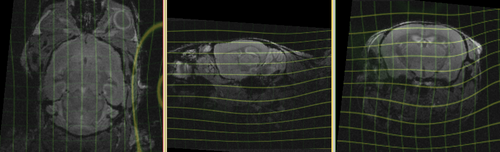

shown are, from left to right, panels of axial, sagittal and coronal views.

registered brains after 5x5x5 nonrigid BSpline alignment registered brains after 5x5x5 nonrigid BSpline alignment

deformation visualized by grid overlay deformation visualized by grid overlay